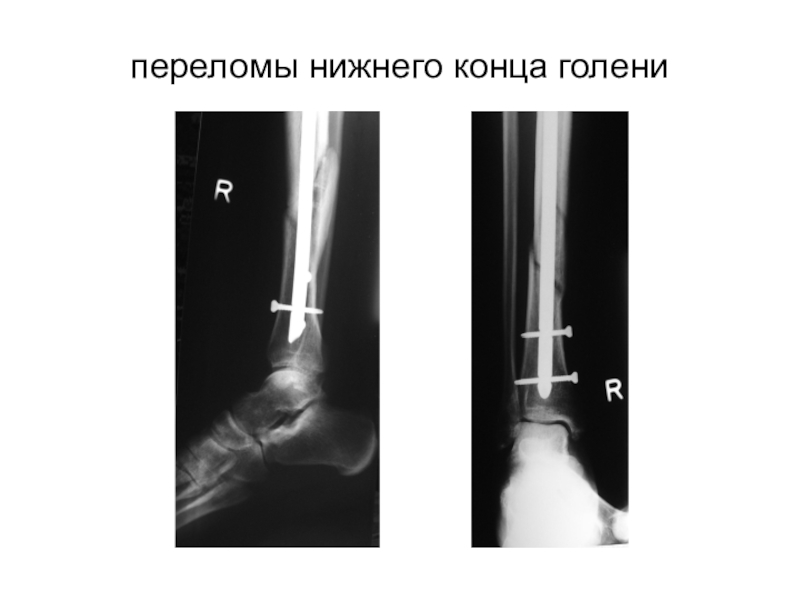

Слайд 36переломы нижнего конца голени

переломы нижнего конца голени